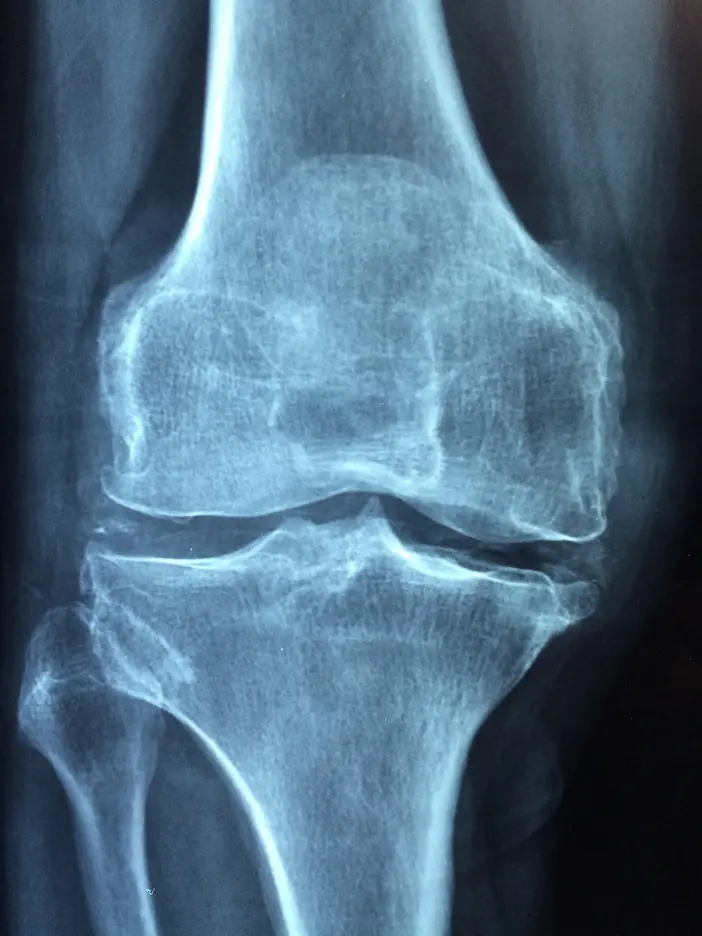

Osteoporoza este o boală care determină o scădere a densității și rezistenței oaselor, sporind riscul de fracturi. În Japonia, se estimează că peste 15 milioane de oameni suferă de această afecțiune, cele mai frecvente și debilitante fiind fracturile de compresie vertebrală, ce necesită adesea îngrijire pe termen lung.